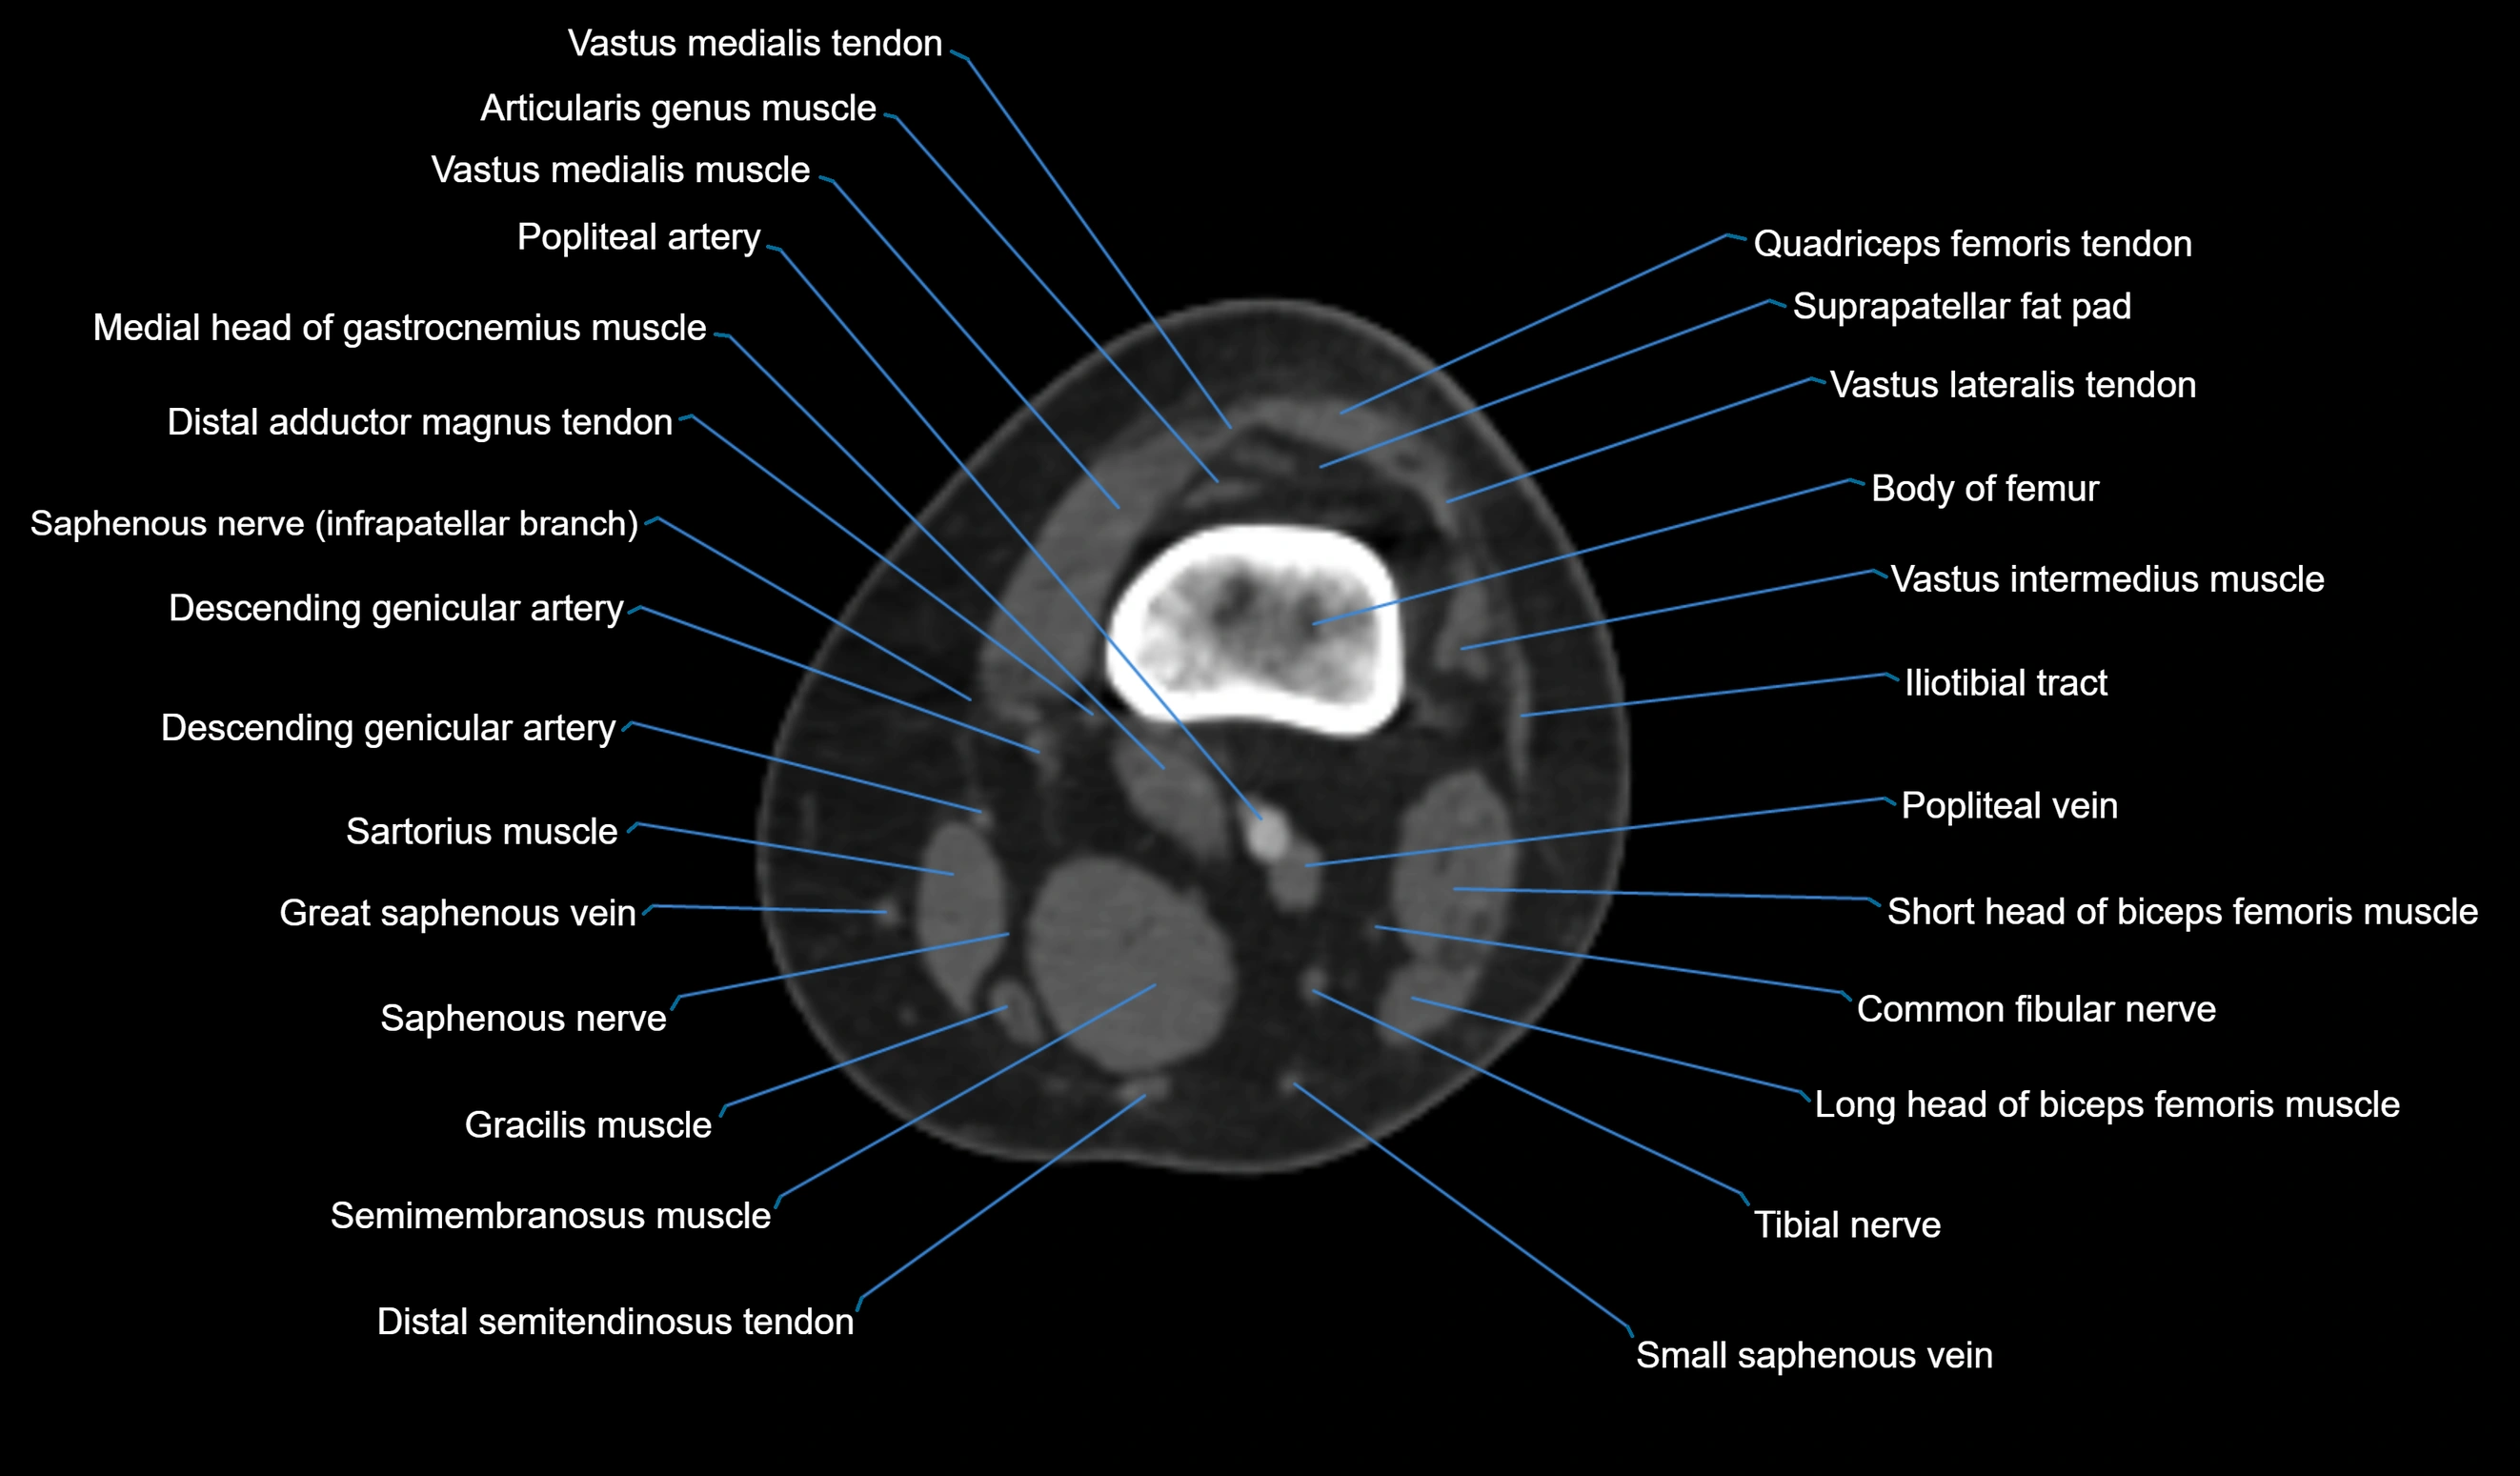

- Common fibular nerve

- Descending genicular artery (Articular branches)

- Descending genicular artery (Saphenous branch)

- Distal adductor magnus tendon

- Popliteal artery

- Popliteal vein

- Saphenous nerve

- Sartorius muscle

- Semitendinosus muscle

- Small saphenous vein

- Tibial nerve

- Vastus lateralis muscle

- Vastus medialis muscle